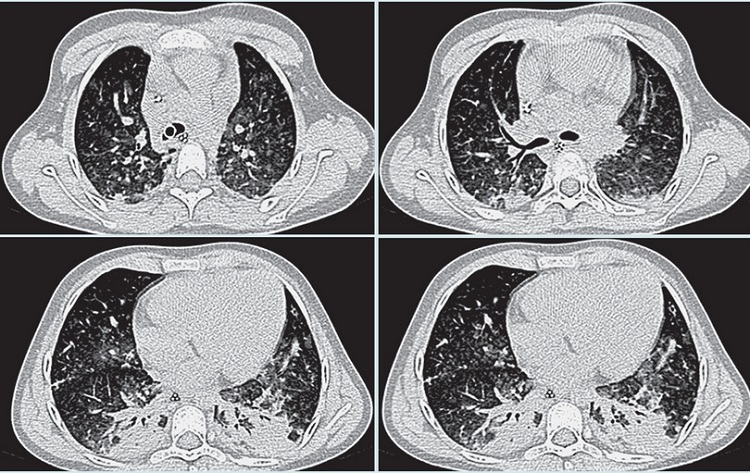

En los exámenes de laboratorio destacó bicitopenia (leucopenia con neutropenia y trombocitipenia). La radiografía de tórax mostró cardiomegalia, rectificación del cono de expulsión de la arteria pulmonar e infiltrado intersticial reticulonodular bilateral, con patrón en vidrio despulido basal derecho (Figura 2). Una semana después presentó insuficiencia respiratoria aguda para la cual requirió de ventilación mecánica por 11 días, con mejoría clínica con manejo intensivo. Se valoró tomografía computada de alta resolución (TCAR) pulmonar en la que se observó patrón en mosaico bilateral, con áreas de ocupación alveolar e importante aumento del calibre de las estructuras vasculares (Figura 3).